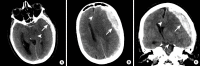

Intracranial hemorrhage is common and is caused by diverse pathology, including trauma, hypertension, cerebral amyloid angiopathy, hemorrhagic conversion of ischemic infarction, cerebral aneurysms, cerebral arteriovenous malformations, dural arteriovenous fistula, vasculitis, and venous sinus thrombosis, among other causes. Neuroimaging is essential for the treating physician to identify the cause of hemorrhage and to understand the location and severity of hemorrhage, the risk of impending cerebral injury, and to guide often emergent patient treatment. We review CT and MRI evaluation of intracranial hemorrhage with the goal of providing a broad overview of the diverse causes and varied appearances of intracranial hemorrhage.